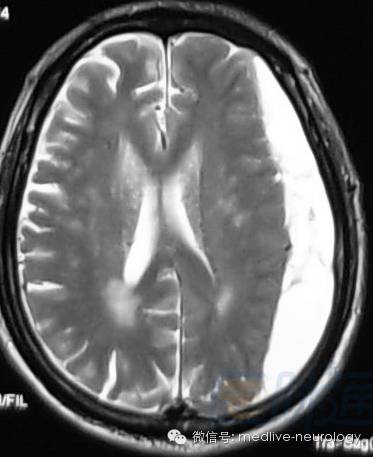

然后解决第三个问题,轻松一下,图来啦,让我们巩固一下今天学习的成果,均为先T1,后T2。

超急性期(<24h):右侧脑室旁

急性期(1-3d):右枕叶